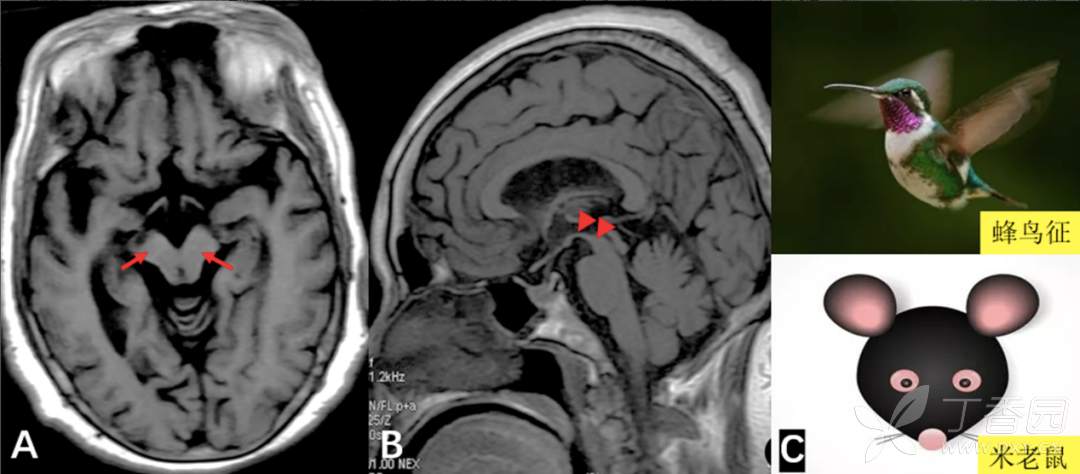

图 4. 进行性核上性麻痹(PSP)

A. 轴位 T1WI 示中脑前后径缩短,呈「米老鼠征」(红色箭);B. 矢状位 T1WI 示中脑顶端平坦或凹陷,呈「蜂鸟征」